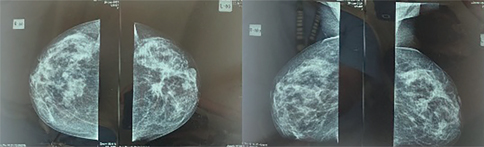

X-ray-based conventional mammography is a routine approach worldwide for breast screening (Figure 1). Several variations of x-ray-based imaging (XBI) technique is available, for example, digital breast tomosynthesis (DBT), and contrast-enhanced digital mammography (CESM), each with its own advantages and disadvantages (1, 3, 6).

Figure 1. Breast cancer mammography imaging: Left, craniocaudal view. Right, mediolateral oblique view. Image was provided by Division of Oncology, Department of Surgery, Faculty of Medicine, Universitas Sumatera Utara.